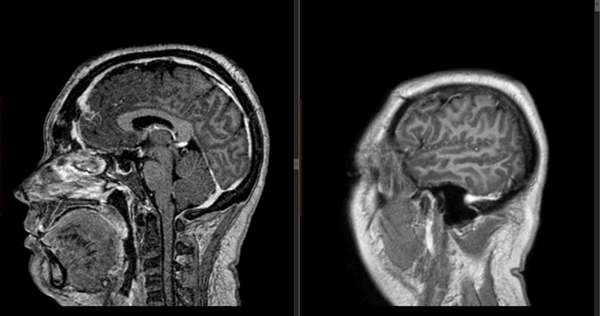

Figura 1: RM en secuencia T1 cortes a) 1axial, se observa lesión espontáneamente hiperintensa y su relación con vasos del polígono de Willis. b) RM en secuencia T1 corte sagital, donde se observa extensión supraselar de la lesión comprimiendo lamina terminalis

Figura 7: RM T1 con gadolinio cortes sagital y coronal que evidencian ausencia de lesión tumoral.